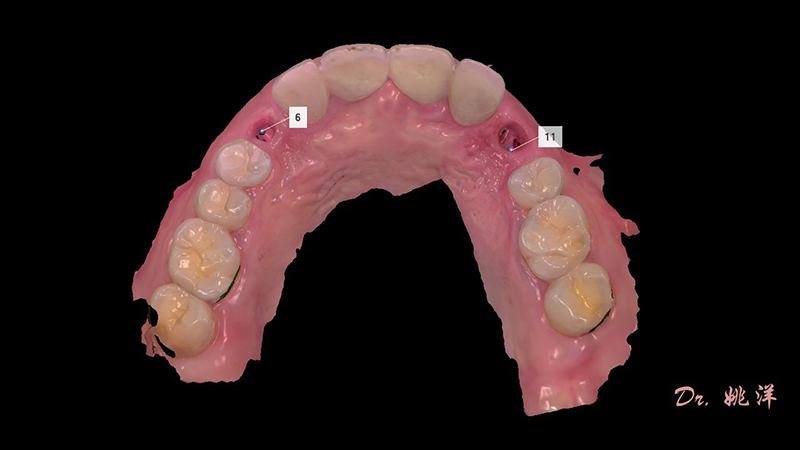

種植后數(shù)字化取模,前牙美學(xué)間隙精確分配

從最終修復(fù)效果可以看出:23,24間隙不足修復(fù)兩顆,修復(fù)為1顆牙。因為經(jīng)過數(shù)字化設(shè)計和精確導(dǎo)航植入,修復(fù)體齦緣協(xié)調(diào)自然